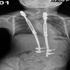

بمجمع د. سليمان الحبيب بالعليا إصلاح انحرافات العمود الفقري للأطفال بتقنيات «V.E.P.T.R»

بمجمع د. سليمان الحبيب بالعليا إصلاح انحرافات العمود الفقري لل...